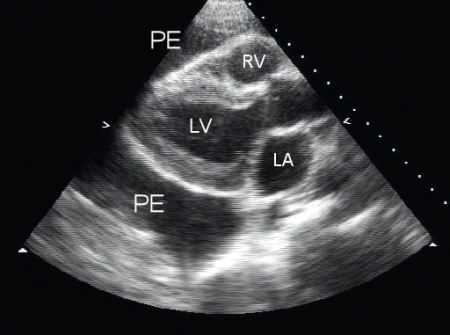

Transthoracic echocardiography is the investigation of choice for a suspected pericardial effusion. It is a non-invasive and effective diagnostic modality. As well as confirming the diagnosis, echocardiography allows the operator to evaluate the size and haemodynamic effects of the effusion.[7]

An echo-free space between the two layers of the pericardium indicates the presence of an effusion.[Figure caption and citation for the preceding image starts]: Parasternal long-axis view of a pericardial effusion (PE); LA = left atrium, LV = left ventricle, RV = right ventricleFrom the collection of Dr Rajdeep Khattar [Citation ends].

General echocardiographic assessment of pericardial effusion includes:

Size

The maximum end-diastolic effusion thickness (distance between epicardial and parietal layers of the pericardium) is measured and the effusion size is graded as:

Trivial (seen only in systole)

Small (<10 mm)

Moderate (10-20 mm)

Large (>20 mm)

Very large (>25 mm)